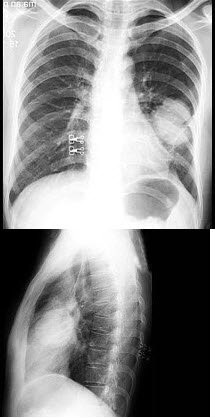

D.前列腺支架置入

男,1岁零8个月,生长发育差,易患呼吸道感染,心悸气促,心脏正、侧位片检查如图所示,正确的描述和诊断是()

A.正位示心影向两侧扩大,心尖左移

B.肺纹理增多

C.侧位示心前间隙变窄,心后食管前三角间隙消失

D.房间隔缺损

E.室间隔缺损